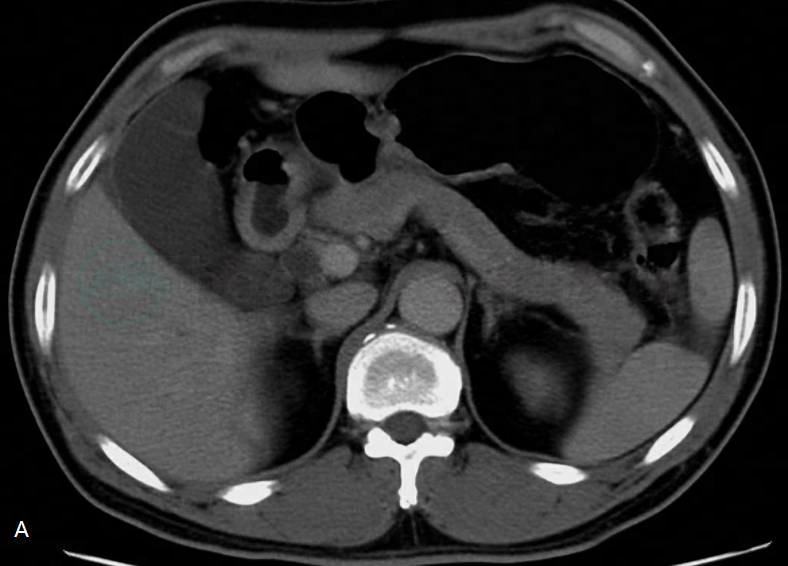

○ CT表现为胃内脂肪密度占位性病变,密度均匀一致,增强扫描不强化(图1)。如果肿物内有软组织密度、有分隔及肿物分叶不规则等征象,提示为脂肪肉瘤之可能。

图1 胃窦部黏膜下层纤维脂肪瘤

A、B. CT增强扫描横断面示胃窦近后壁处凸向胃腔内生长的结节影(白箭),大小约3.0cm×2.0cm,边界清楚,病变密度略不均匀,以脂肪密度为主;C、D. 胃气钡双对比造影:胃窦小弯侧见一充盈缺损(黑箭),凸向胃腔内,大小约1.9cm×3.3cm,局部黏膜规则,未见龛影,胃壁柔软